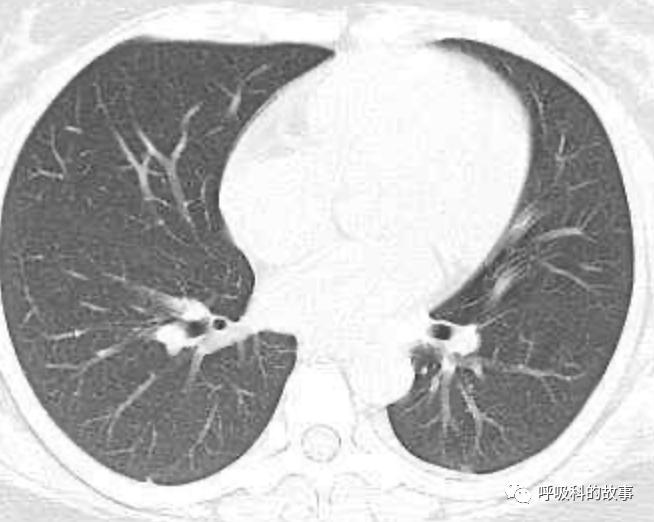

可是在6月26日(往院第18天)仍持续发热的情况下复查肺部CT,肺部病灶已明显吸收了。那么患者发热的原因到底是什么呢?为什么患者高热的情况下血白细胞不升反降,C反应蛋白也没有明显增高?这个时候消化科医生也迷茫了,这可怎么办?于是请感染科和呼吸科医生一起会诊,共商计策。